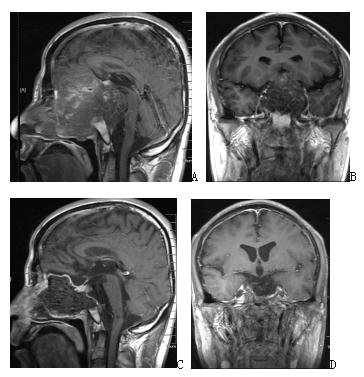

图2. A、B手术前增强磁共振,提示复发巨大全斜坡脊索瘤;C、D内镜经鼻手术后增强磁共振,提示肿瘤全切。